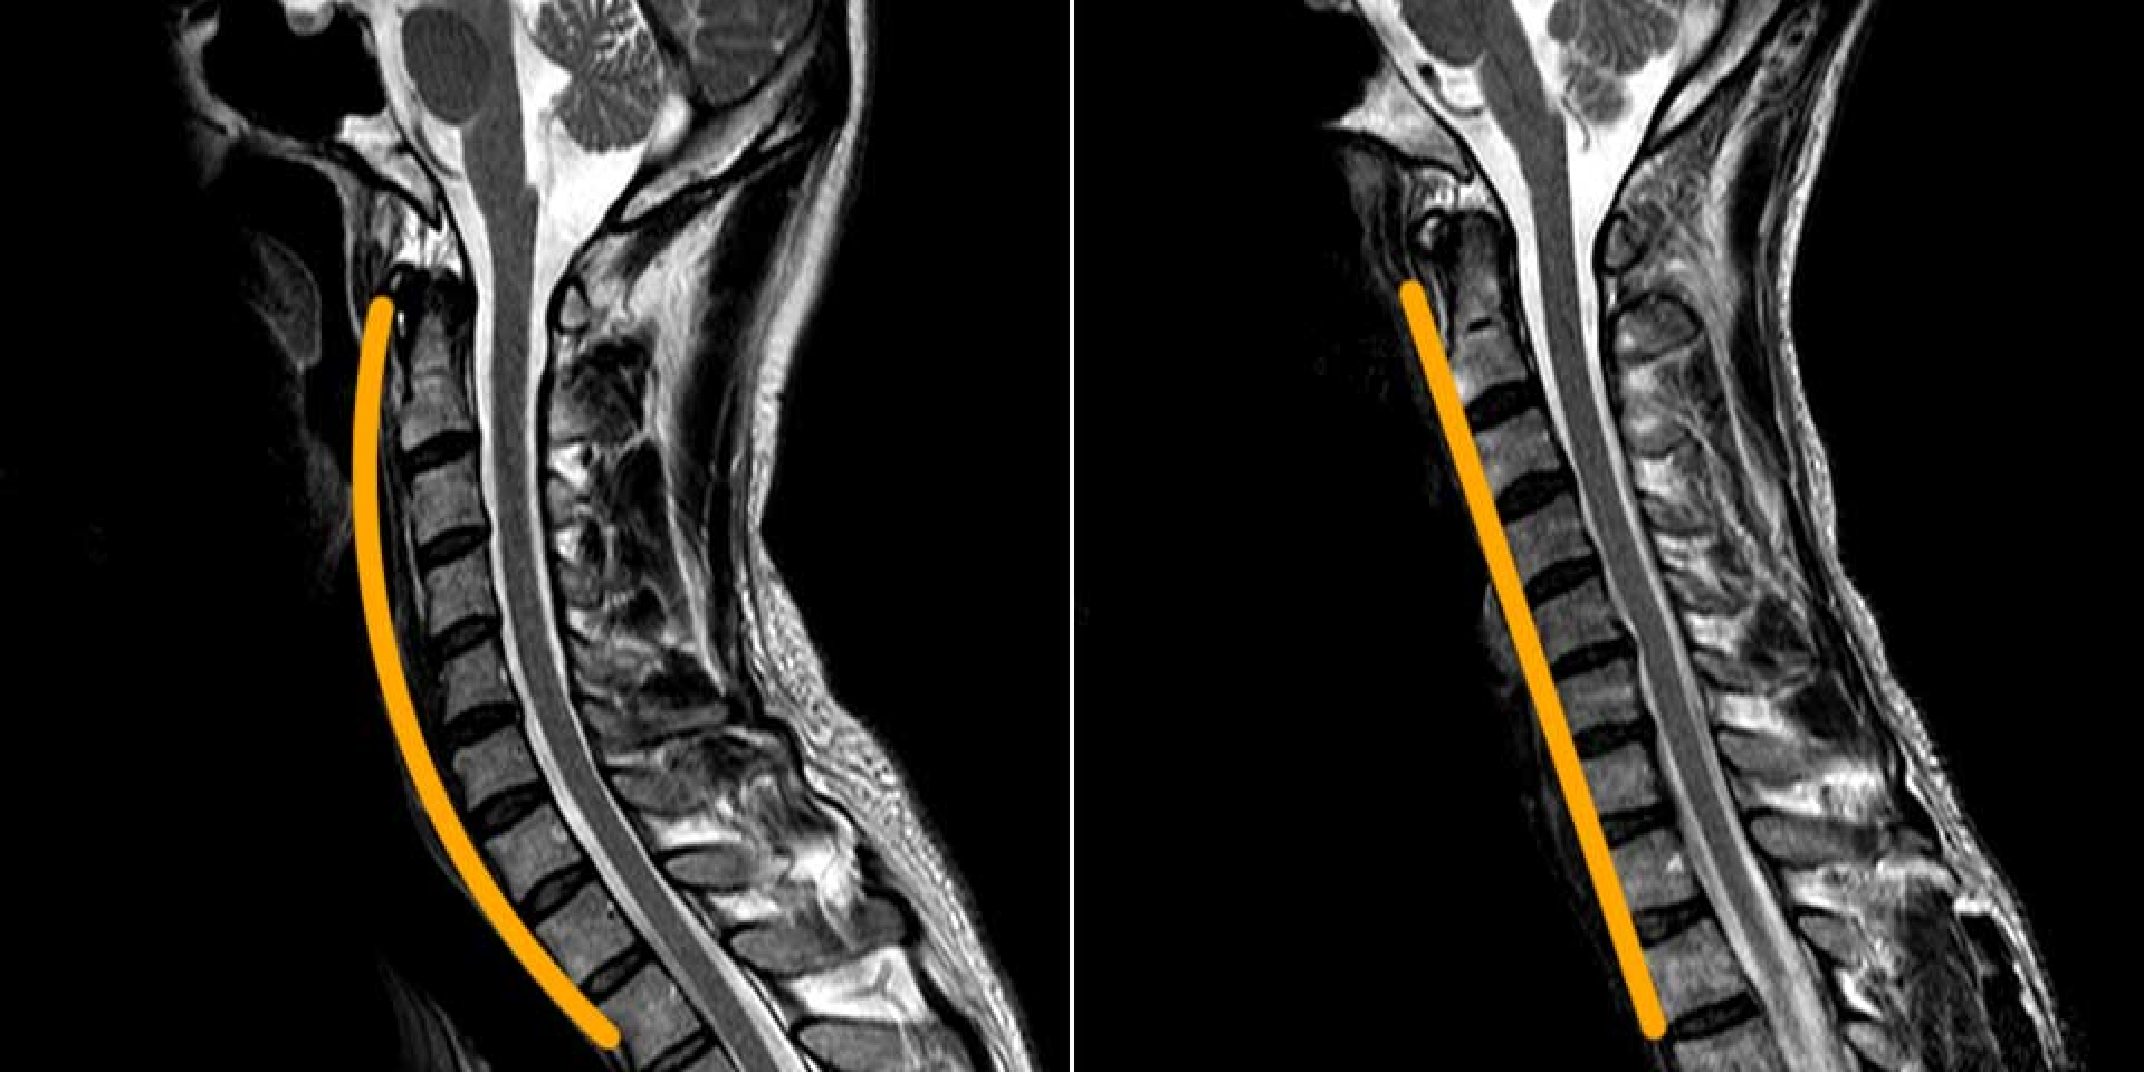

No.04 脊椎検査|

運動機能を守るための精密な脊椎検査矢印のイラスト

脊椎疾患の早期発見と予防管理

脊椎(背骨)は、二足歩行をする人類にとって重要な役割を果たしていますが、

加齢や日常のストレスにより、頚椎症や椎間板ヘルニアなどさまざまな脊椎疾患が引き起こされる可能性があります。

当院では、MRIによる詳細な脊椎検査を実施し、これらの病気を早期に発見し、適切に対処します。

脊椎検査の重要性

頚椎や腰部に起こる障害は、腰痛症や脊椎管狭窄症など、老年期の生活の質に大きな影響を与える病気です。

MRIを使用した詳細な検査により、脊椎の状態を把握し、運動機能を維持するための予防管理を行います。

MRIによる精密検査

正常時頚椎とストレートネック

脊椎検査のイメージ画像

生活の質を守るための予防と治療

脊椎の病気は、日々の運動機能に影響を及ぼすため、早期に発見し適切な治療を行うことが重要です。

当院の脊椎検査は、痛みのないMRI検査で短時間に完了し、生活の質を守るための重要な情報を提供します。